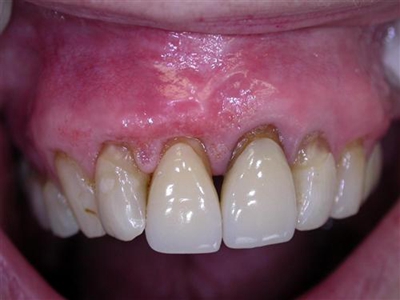

牙龈退缩上牙龈萎缩露出深黄色牙根图

牙龈退缩导致上牙的牙龈严重萎缩,牙根暴露,齿间缝隙大,侧面堆积黄色菌斑。牙龈退缩后根面长久暴露,患者会有牙齿敏感等不适症状。